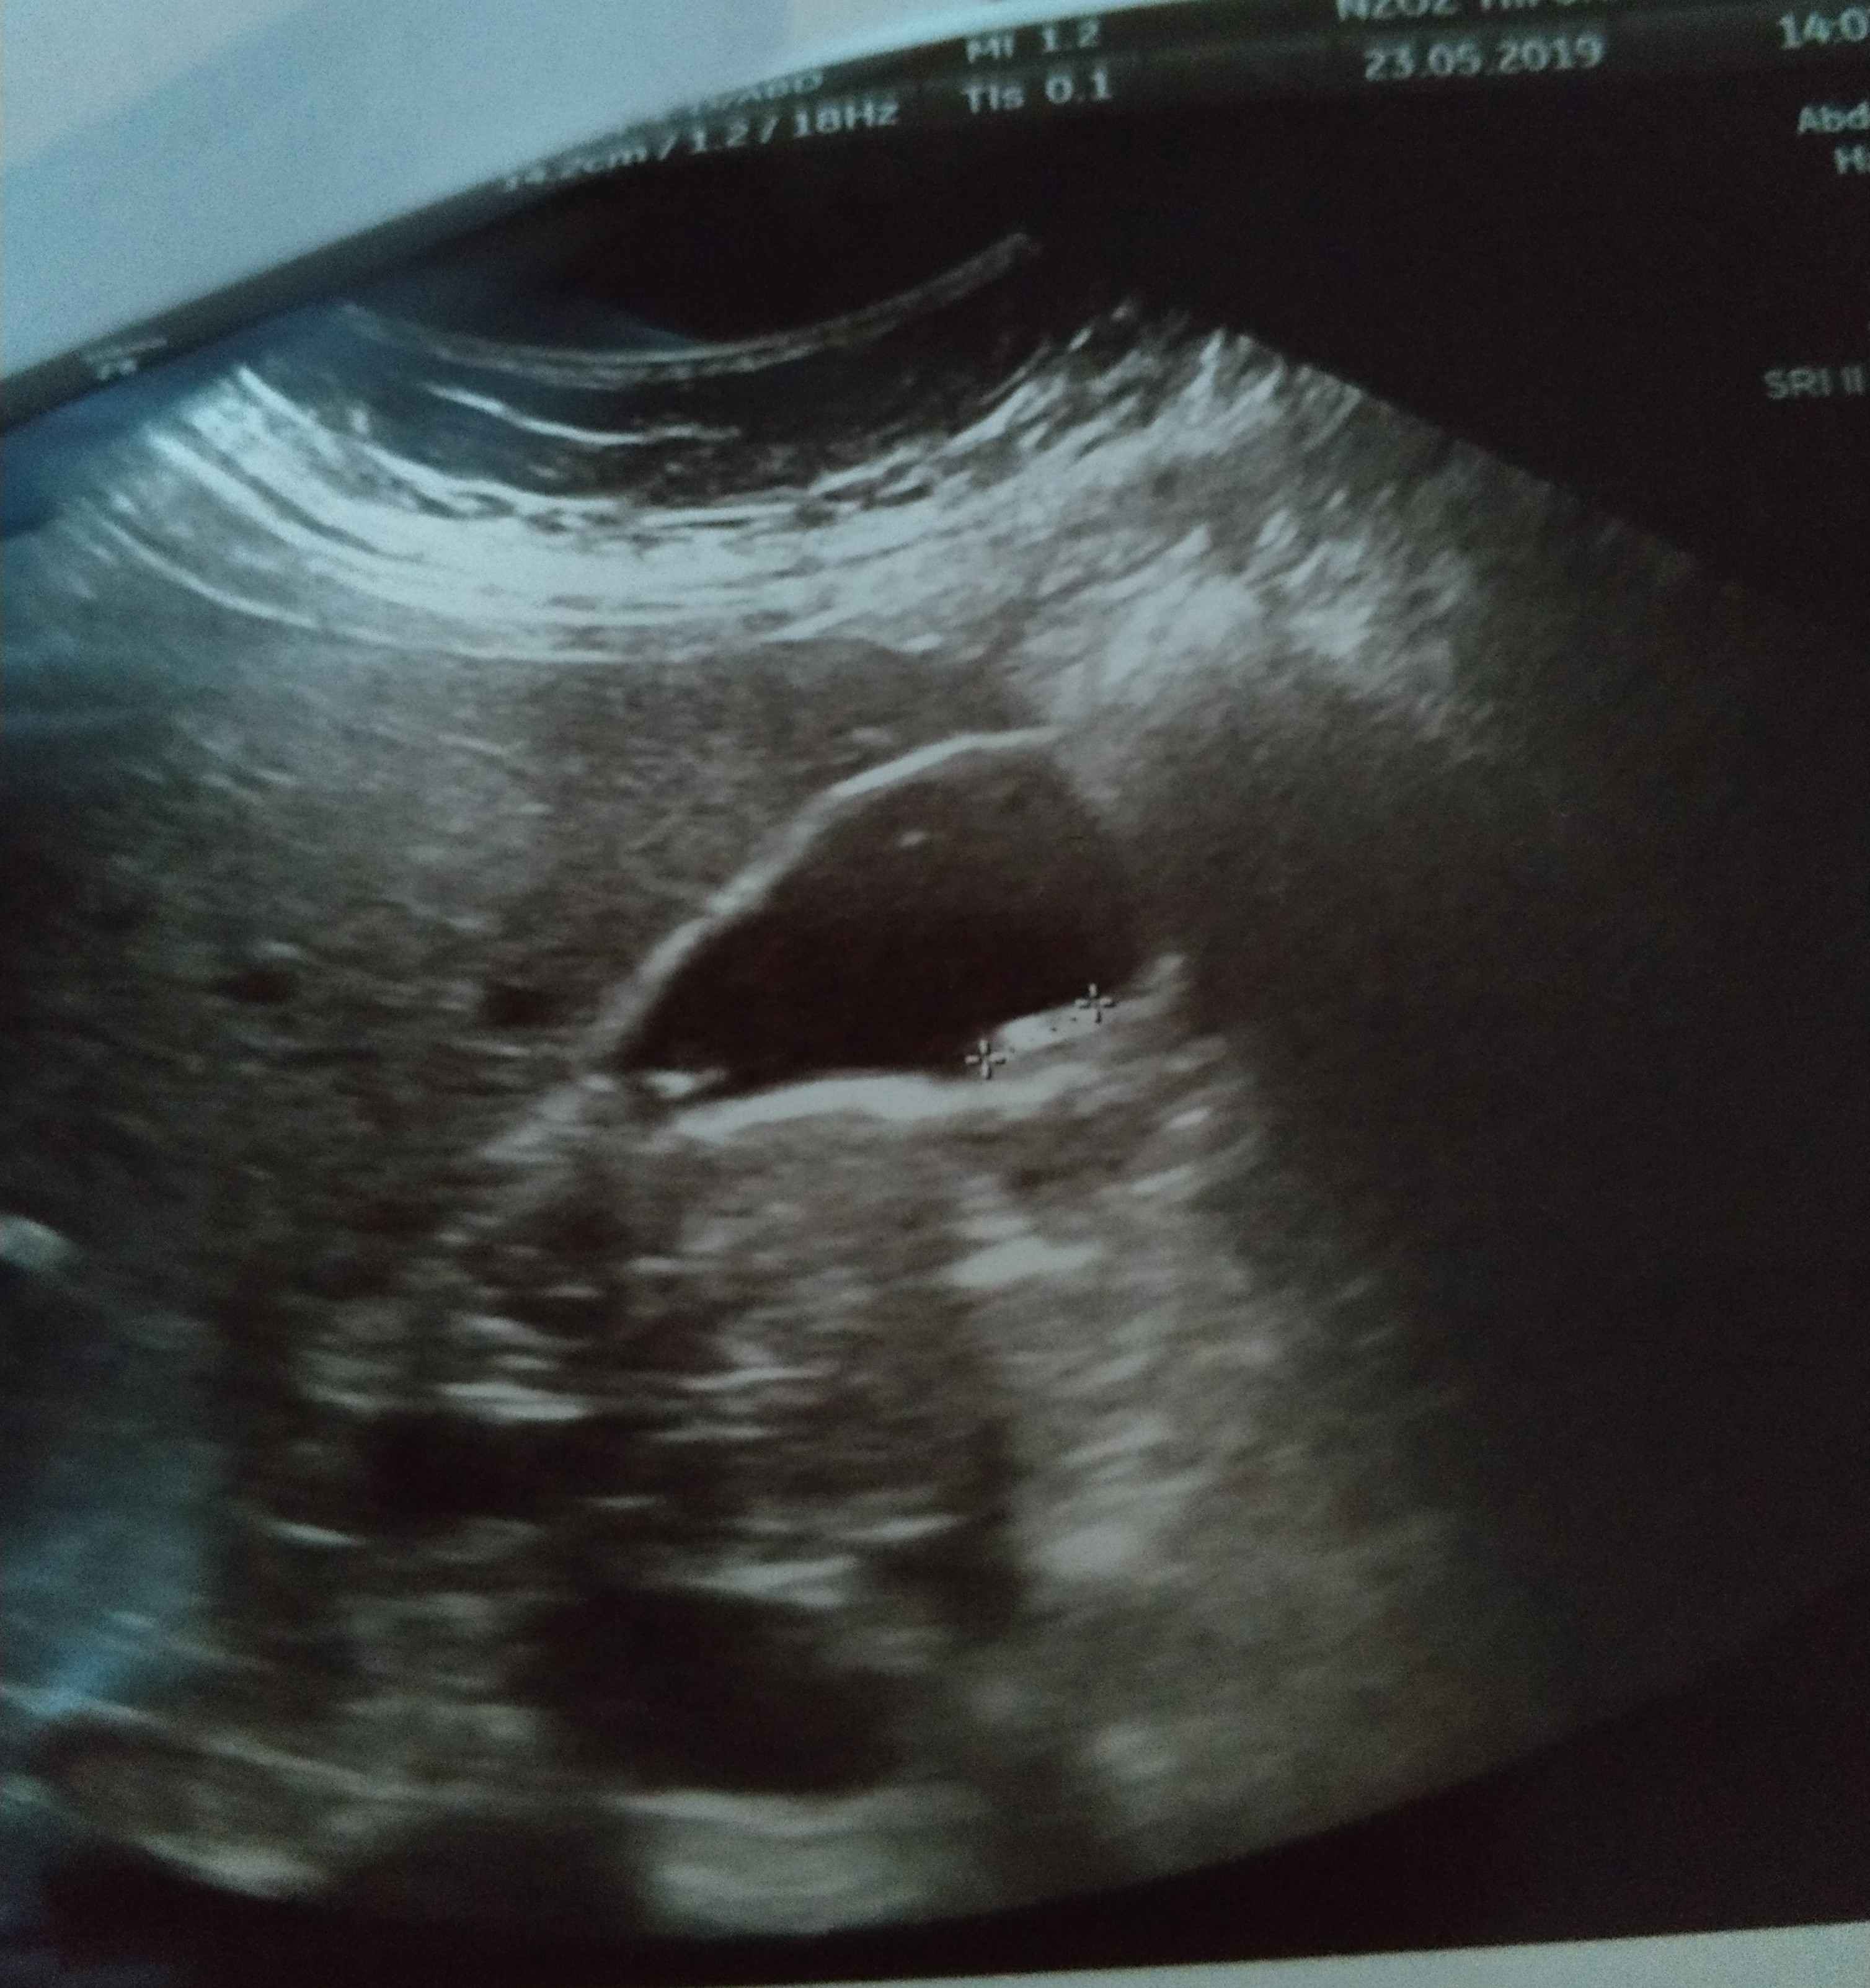

Jestem dzis po Usg brzucha. I juz nie musze isc na gastroskopie. Mam diagnoze. Bardzo liczne kamienie w woreczku zolciowym o wielkosci od 4 do 10mm.

Przedstawiam wam moich niechcianych lokatorów..

IMG_20190523_210759.jpg